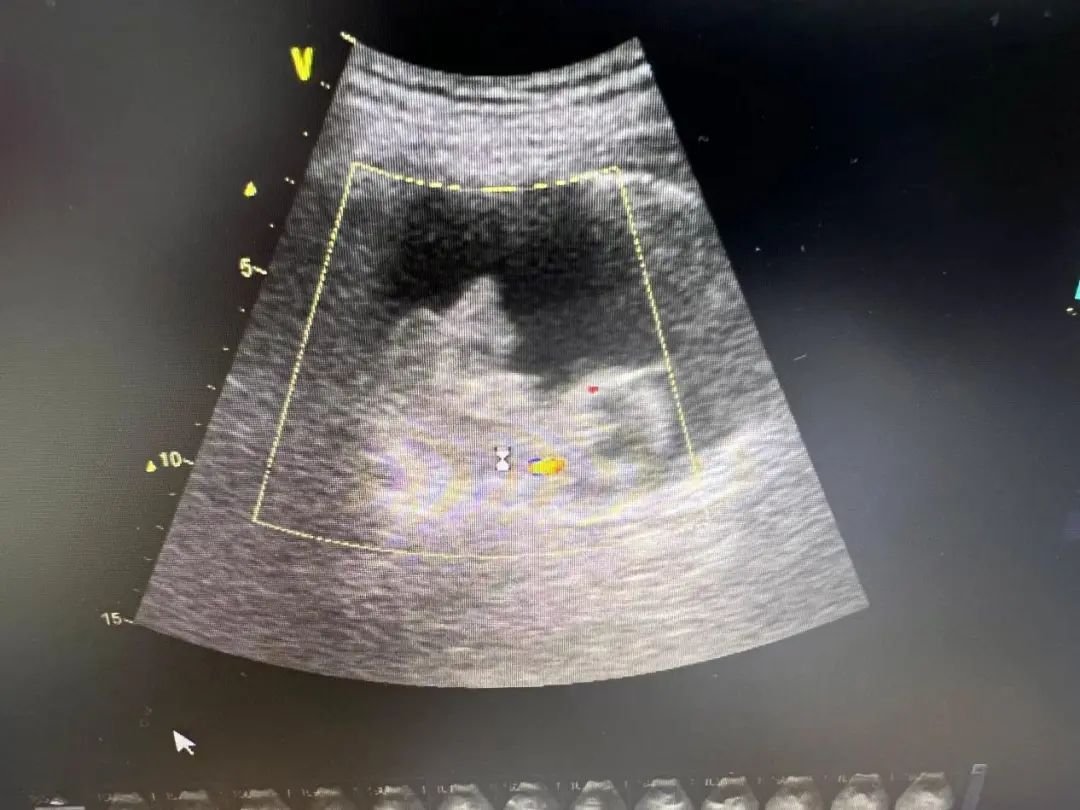

术中发现老人的前列腺非常大,两侧叶已经把尿道挤压变形了,膀胱内结构紊乱,有大量小梁小室,膀胱内可以看到有一个巨大的血块形成,血块里还包裹着一枚2cm左右的结石,这也许就是老人血尿的元凶。

医生们首先将膀胱内血块清除,再使用激光将膀胱内结石击碎取出,考虑到患者年龄偏大,手术风险也会随手术时间延长而增大,在反复检查膀胱内无活动性出血后,医生留置三腔导尿管迅速结束手术。